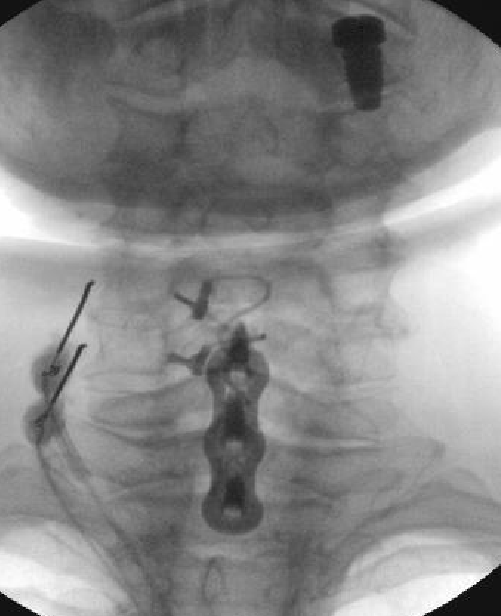

Nasty neuritis. This is 80 degrees 90 seconds.

These images look great. Sorry it happened? Steroid?

Lyrica Rx sent in, and we're starting it for chronic pain (and neuritis). She gets a shoulder scope in two weeks for a large RCT. I like antineuropathics (gabapentin 100mg HS or BID) perioperatively in general. I wish they were given 2 weeks before and after ALL orthopedic surgeries.

Dexamethasone given before RFA needles were removed.

Why are you doing RFA at a fused level?

i believe medicare will not cover RFA of a fused level.

i saw that too, but when you look at the AP images...

why would a fused level hurt?